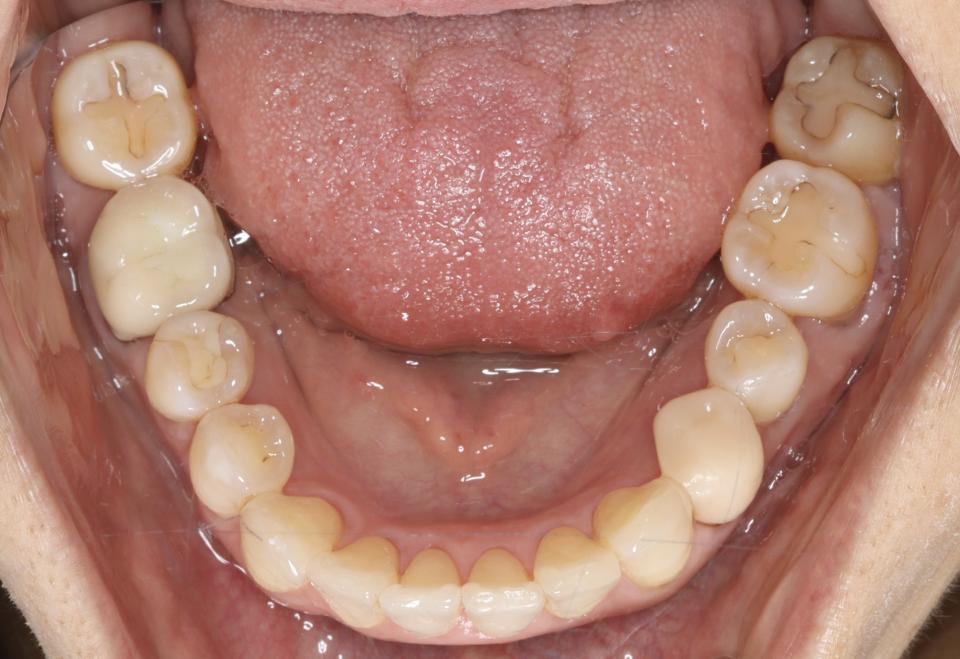

上顎前突(出っ歯)のマウスピース型矯正治療例

矯正治療後

マウスピース型の矯正治療装置を使用し、歯のやすり掛け(IPR)を行いました。

現在はマウスピース型のリテーナーでで後戻りの防止をして定期的にチェックをしています。

| 年齢・性別 | 40代女性 |

| 矯正治療期間 | 2年9か月 |

| 抜歯の有無 | なし |

| 治療費 | 1,005,000円(検査/診断/施術料) |

歯の移動に伴い痛みを感じる場合がある 治療後保定装置を使わないと後戻りを生じる